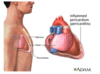

What is the typical history of pericarditis?

- Secondary to viral illness (recent cough)

- Retrosternal sharp chest pain localised to front of chest

- Aggravated with inspiration, cough, lying flat

- Eased by sitting up and leaning forward

- May hear pericardial rub

What would an ECG look like when someone has pericarditis?

Widespread saddle shaped ST elevation over a number of leads